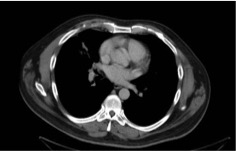

The patient was discharged on the 12th day of admission and maintained on oral ciprofloxacin and trimethoprim-sulfamethoxazole (TMP-SMX) for 13 weeks and daily ertapenem infusions for 4 weeks. He remained on daily warfarin. Follow-up chest CT scans at 4-week follow-up revealed complete resolution of the pulmonary abscess and no pleural effusion (Figure 2).

Figure 2. CT scans at 4 weeks showed that the lung lesion had completely resolved after appropriate treatment.